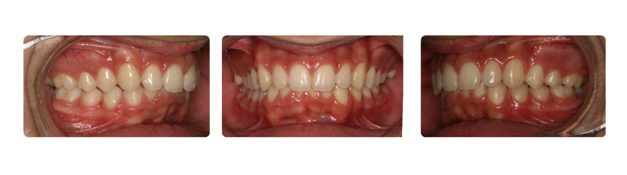

| پس از پایان درمان متحرک وسپس درمان ثابت فکین ناهنجاری فک و بی نظمی دندانها برطرف شده است: |

![]() |

| پس از گذشت دو سال از پایان درمان نیز همچنان دندانها و فک ایده ال وهمچنین مطلوبتر نیز شده است. |